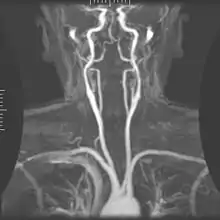

Magnetic resonance angiography (MRA) generates pictures of the arteries to evaluate them for stenosis (abnormal narrowing) or aneurysms (vessel wall dilatations, at risk of rupture). MRA is often used to evaluate the arteries of the neck and brain, the thoracic and abdominal aorta, the renal arteries, and the legs (called a "run-off"). A variety of techniques can be used to generate the pictures, such as administration of a paramagnetic contrast agent (gadolinium) or using a technique known as "flow-related enhancement" (e.g., 2D and 3D time-of-flight sequences), where most of the signal on an image is due to blood that recently moved into that plane (see also FLASH MRI).[51]

Techniques involving phase accumulation (known as phase contrast angiography) can also be used to generate flow velocity maps easily and accurately. Magnetic resonance venography (MRV) is a similar procedure that is used to image veins. In this method, the tissue is now excited inferiorly, while the signal is gathered in the plane immediately superior to the excitation plane—thus imaging the venous blood that recently moved from the excited plane.[52]